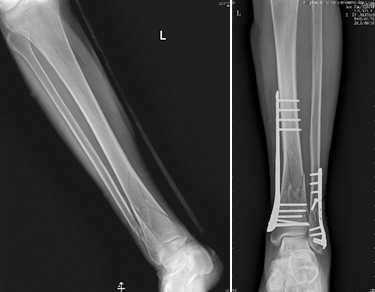

1、复杂关节骨折以及多发创伤的治疗:

随着交通运输、建筑行业的发展,高能量、高暴力的骨折创伤日益多见,特别是发生在关节部位的骨折,若采用传统的石膏固定,则会导致关节部位的僵硬、挛缩。北京清华长庚医院创伤骨科中心诸位医师,通过国际内固定学会(AO-ASIF)相关培训,科学、合理的应用AO原理,对复杂的关节骨折实施手术治疗,可使患者获得早期的功能锻炼,以求得最好的功能恢复。同时创伤骨科中心应用国际最新的微创技术治疗骨折以及多发创伤,进一步减少病人痛苦,加快患者康复,获得良好的效果。

肢体骨折的髓内针微创治疗                  肢体骨折的经皮钢板微创治疗

肢体骨折的经皮钢板微创治疗               复杂关节骨折的手术治疗